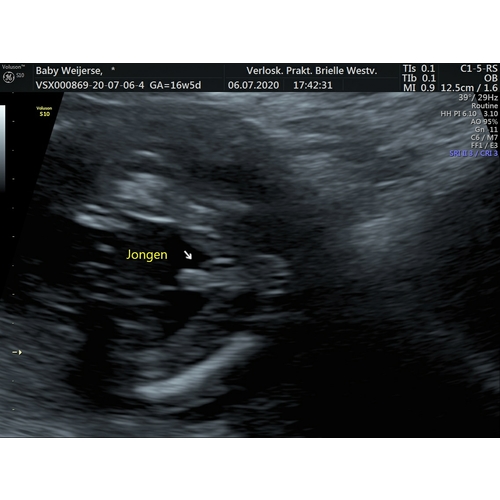

Nja ik wil mijn echo van gisteren ook nog wel delen. Zelf lag ik compleet dubbel hoe vriendlief de foto in handen kreeg.

We wisten het geslacht al met 13 weken. Zijn reactie was “nou nu weet ik zeker dat we een zoon krijgen, overduidelijk”

😂😂😂

Hij begreep niet direct dat het piemeltje met het kleine pijltje word aangewezen 😂